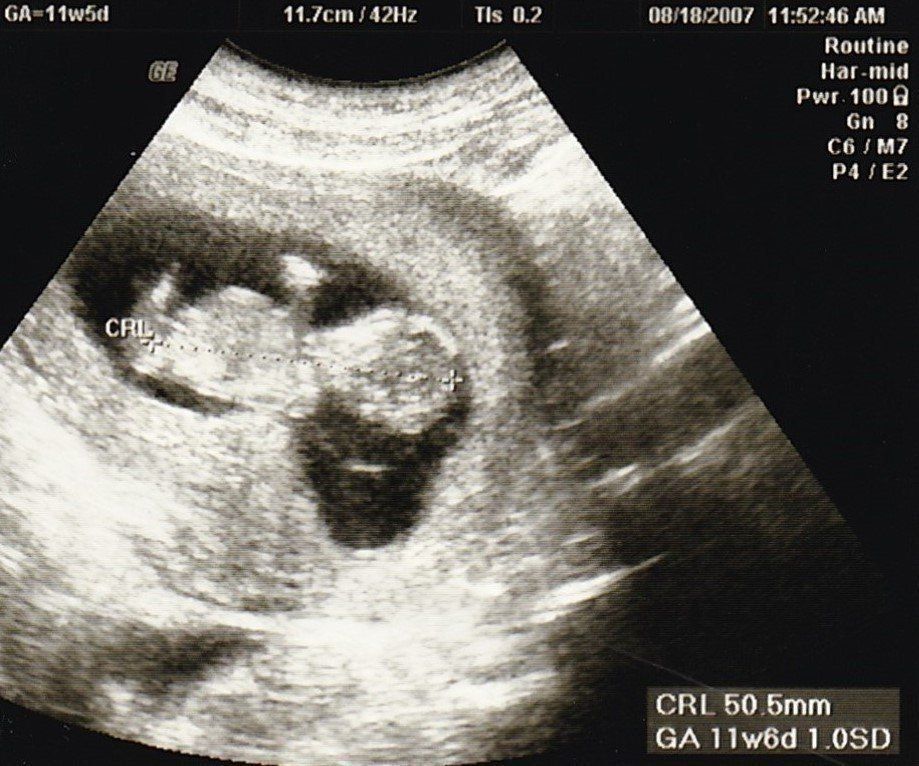

妊娠11週目のエコー写真

産院では、動画で赤ちゃんが動く映像を見せてくれて、検診に行くのが楽しみでした。

この頃、胎児染色体検査(ダウン症かどうかの検査)をするかを決めたり、“ソフロロジー法”の資料を読んだりすることで、私はどういう出産をしたいかを考えるようになりました。(胎児染色体検査はその結果によって産むか産まないかを考えることをしたくなかったので、受けるのをやめました。)